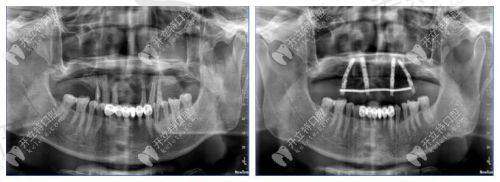

医院在种植领域先引入“3D导板导航种植系统”,术前通过口腔CT扫描获取牙槽骨三维数据,计算机模拟种植角度、深度及咬合关系,定制个性化导板,术中实现“精细定位、微创植入”,将手术时间缩短至30分钟/颗(传统种植需60分钟以上),创伤面积减少40%,术后肿胀轻、修复快。针对半口/全口缺牙患者,采用“All - on - 4即刻负重技术”,仅需植入4颗种植体即可修复半口牙齿功能,当天完成种植与牙冠修复,解决传统全口种植需6 - 8颗植体、3 - 6个月修复期的弊端。

数字化矫正技术体系

依托数字化矫正平台,医院实现“数据采集 - 方案设计 - 成效预知 - 全程监控”全流程数字化管理。患者就诊时通过iTero口内扫描仪替代传统硅橡胶取模,避免恶心不适,数据即时上传至矫正设计系统,医生联合计算机算法制定方案,并通过3D动画展示每一步牙齿移动过程,患者可直观了解矫正成效并参与方案调整。矫正过程中,医生通过远程监控系统跟踪牙齿移动情况,及时调整矫治力,确保矫正周期缩短15% - 20%,精细度提升30%。